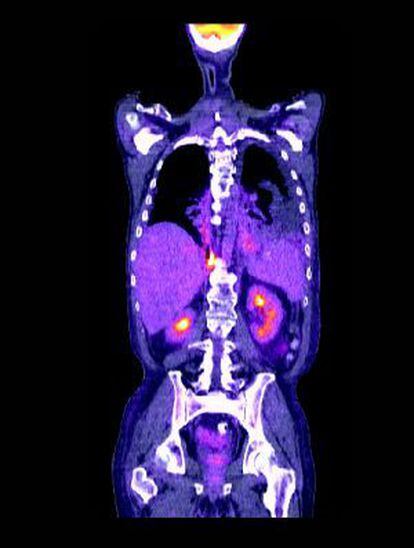

La inmunoterapia ha conseguido sus primeros éxitos contra el cáncer de pulmón. Este abordaje, consistente en activar el sistema inmunitario del paciente para que colabore en la lucha contra las células cancerosas, había fracasado hasta la fecha al intentar usarla en uno de los tumores más frecuentes y mortales, el de pulmón (más de 26.000 casos y de 21.000 muertes en España en 2012, según los datos de la Sociedad Española de Oncología Médica, SEOM). El avance es tan importante que el viernes mereció la primera sesión del Congreso de la Sociedad Americana de Oncología Clínica (ASCO) que se celebra en Chicago.

Aunque el cáncer de pulmón sea el más frecuente de los tratados, en el congreso, al que EL PAÍS ha acudido invitado por Janssen, se ha resaltado también las expectativas que este abordaje abre para otros cánceres, como el de cabeza y cuello, colon e hígado. El nexo común entre todos ellos es un juego de dos proteínas, la PD-1 y la PDL-1, la primera en los linfocitos del sistema inmunitario y la segunda en las células tumorales. Y lo que hacen los fármacos que se han ensayado (el nivolumab, de BMS, y el pembrolizumab, de Merck), en líneas generales, es asegurarse de que la PDL-1 no oculta el cáncer a las defensas del paciente.

En el caso del cáncer de pulmón, el avance es especialmente importante porque, hasta ahora, se había resistido a la inmunoterapia. Se decía que era poco sensible a esos tratamientos, “pero lo que pasaba es que no teníamos el correcto”, dijo Luis Paz-Ares, del Hospital 12 de Octubre de Madrid, que ha participado en los ensayos y fue el encargado de exponer los avances conseguidos. De los distintos tipos de cáncer de pulmón, el trabajo de Paz-Ares se ha centrado en el denominado de células no pequeñas y no escamoso.

La complejidad del nombre es una prueba de que, según avanza el conocimiento, se van acotando más los tratamientos para darles una terapia que se denomina personalizada. La importancia de trabajar con este grupo –y con el de los tumores escamosos, cuyos resultados se presentaran el domingo- es que entre ambos representan el 85% de los cánceres de pulmón, precisamente aquellos que actualmente tienen peor pronóstico. De hecho, la eficacia del nivolumab, según el estudio CheckMate057, va en paralelo a la presencia de la proteína PD-1 en las células. Si, de media, la supervivencia de los pacientes pasa de los 9,4 a los 12,2 meses frente al tratamiento actual con docetaxel, en los que tienen una mayor expresión de la PD-1 pasa de 9,4 a 18, indica Paz-Ares.